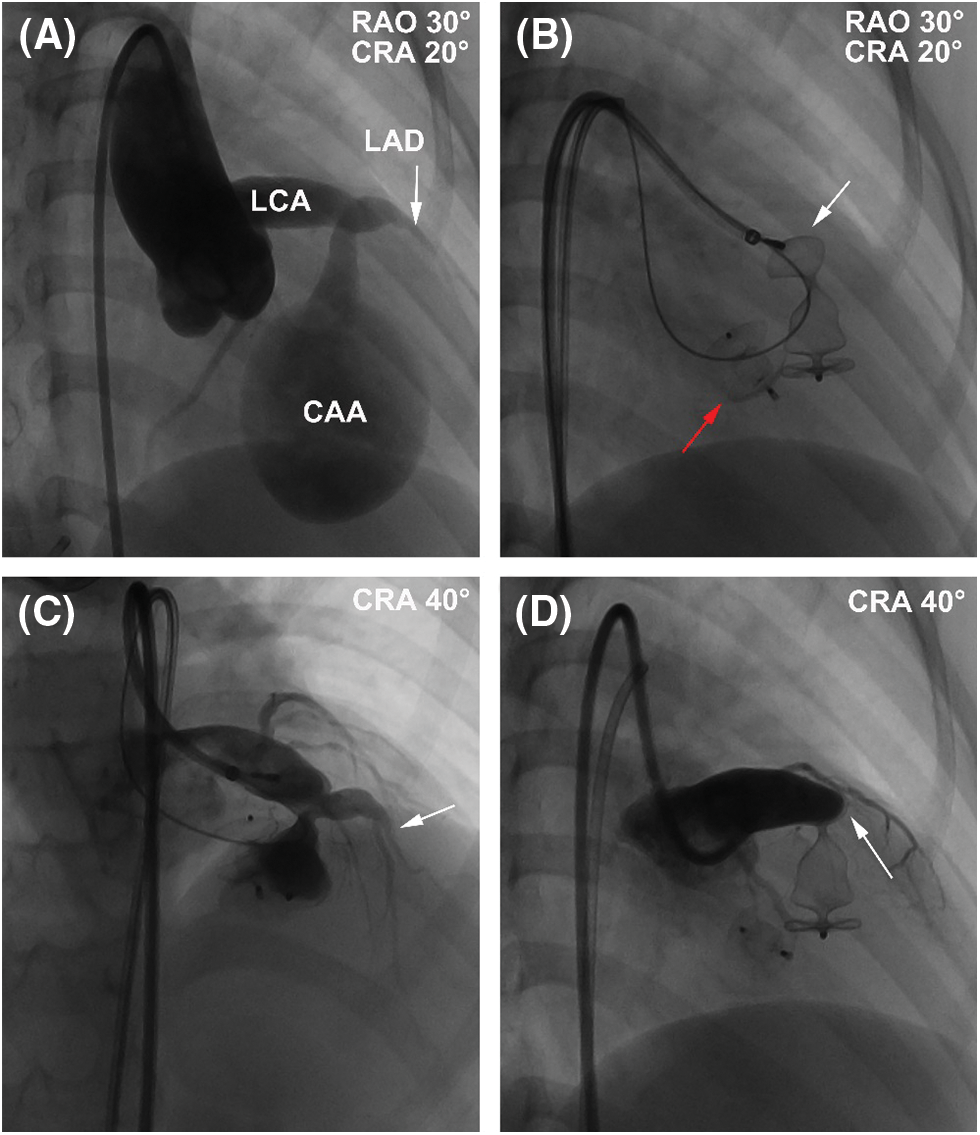

During the procedure, coronary angiography further confirmed the abnormalities in these structures and excluded any other coronary artery lesions (Fig. 3A). The diameters at the inlet and outlet of fistula were 7.2 and 3.5 mm, respectively. An arterial-arterial loop was created, and a 6-Fr sheath was delivered anterogradely through the aneurysm and reached to the drainage site. A 04-04 mm Amplatzer duct occluder II (ADO II, Abbott Structural Heart, Plymouth, MN, USA) and a 12 mm Amplatzer vascular plug II (AVP II, Abbott Structural Heart, Plymouth, MN, USA) were deployed at the outlet and inlet of fistula, respectively (Figs. 3B and 3C). After releasing the AVP II, repeated coronary angiography showed that distal LAD was occluded (Fig. 3D). However, there was no ST-T changes on 12-lead ECG during the procedure. Since the patient was at high risk of ventricular septal hematoma and left ventricular function impairment after incision of the aneurysm, we decided to keep the patient under conservative treatment instead of surgical removal of the device and ended the procedure.

Figure 3: The procedure of transcatheter closure of the LCA-to-LV fistula with giant CAA. (A) RAO 30° and CRA 20° projection of left coronary angiography showed that the fistula originated from the anterior interventricular branch and drained to LV with an aneurysm of 41 mm × 28 mm in size. (B) A 04-04-mm ADO II (red arrow) was deployed at the outlet of fistula, and a 12-mm AVP II was deployed (white arrow) at the outlet of fistula at RAO 30° and CRA 20° projection. (C) CRA 40° projection of left coronary angiography showed that LAD (arrow) was visible before release of the AVP II. (D) CRA 40° projection of left coronary angiography showed that LAD was obstructed by the AVP II intermediately after release. White arrow indicated the occluded LAD